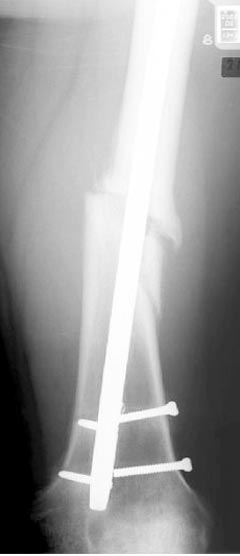

Лечение бедра - ургентное оперативное лечение антеградным с минимально рассверливанием, фиксацией с минимальным диаметром штифта и плюс irrigation and debridment и с закрытием поперечной до 10 см раны на уровне перелома в день поступления.

Снимки представлены: 1 мес; 3 мес; 1 год; 2 года, предоперационные и ротационная КТ грамма

Деформация:

Вальгус- 17 градусов

Рекурватум 5 градусов

Укорочение 2.5см

Ротационно 22 градусов внутренная

Смещение диафиза по поперечнику 75%